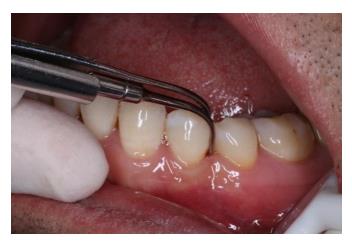

2.齦下刮治